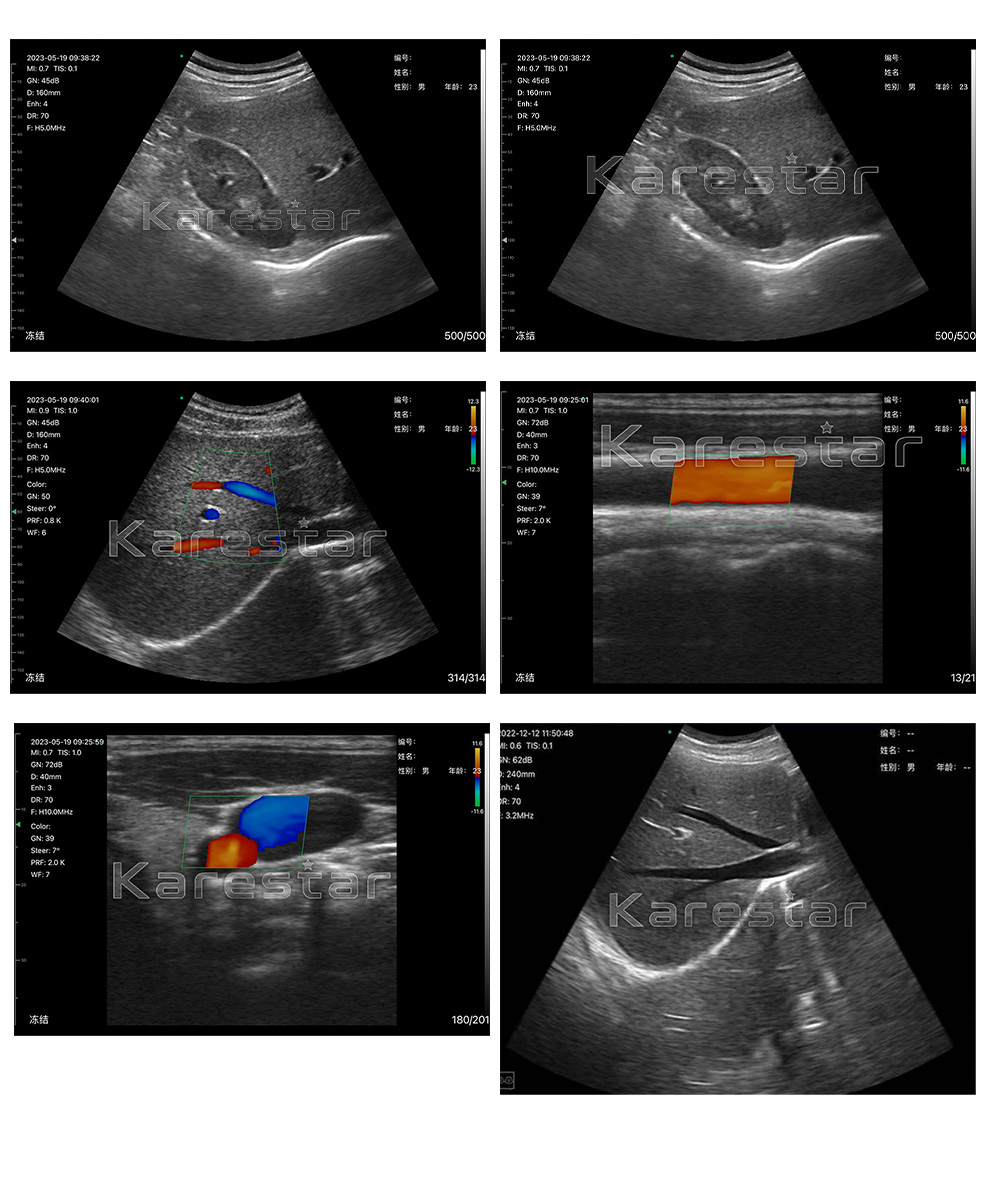

We minimize the components of a traditional ultrasound into a small circuit board built into the probe, and showing image in smart phone/tablet through Wifi transferring. The image can both show in screen and tablet. Image transferring through internal wifi from probe, no need external Wifi signal.